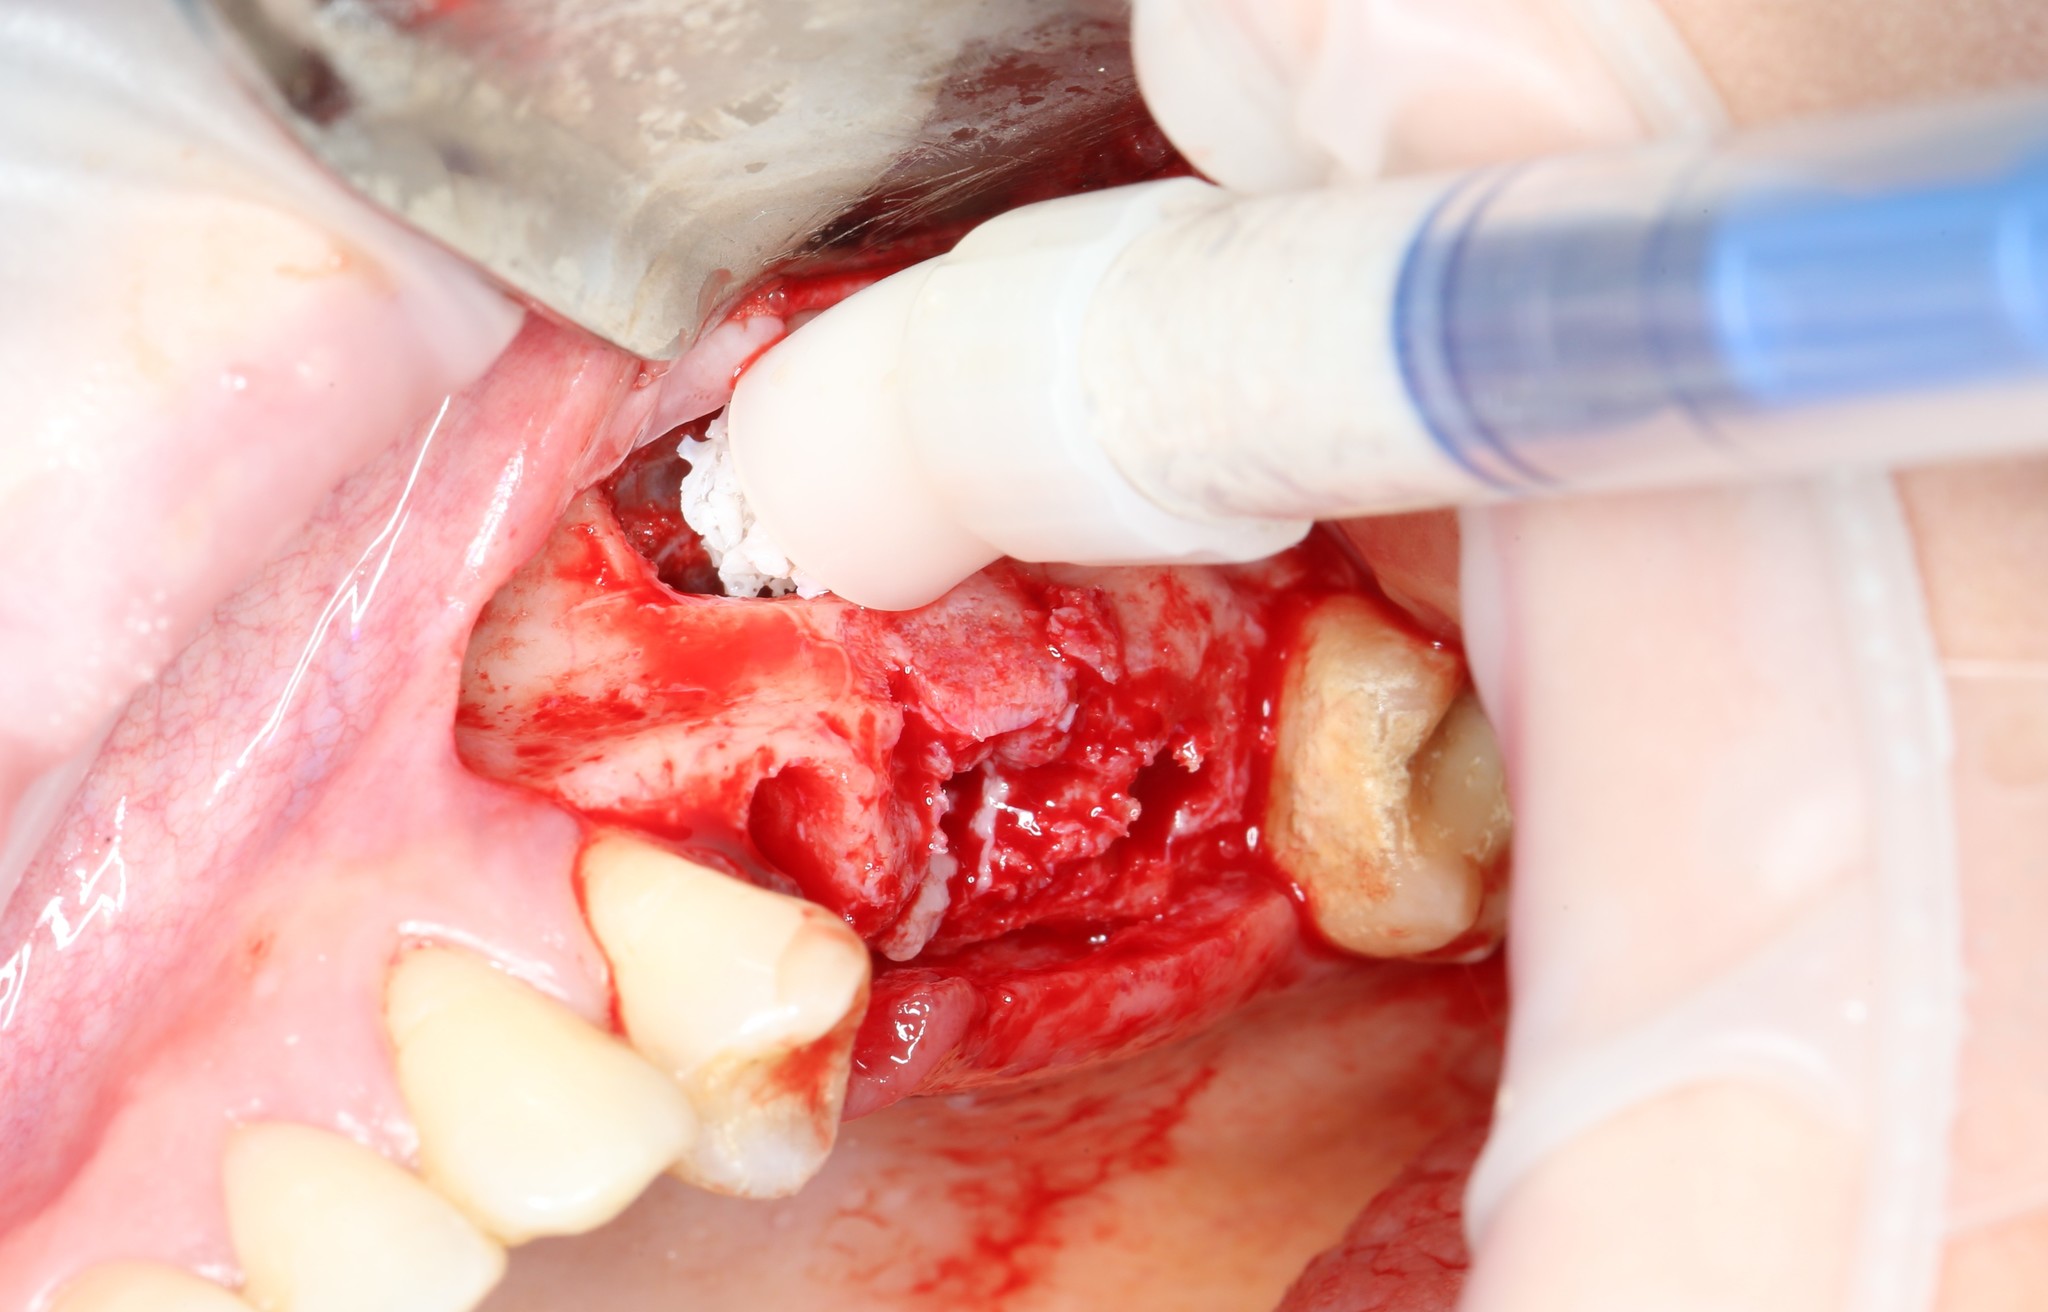

Производится внесение костного материала.

Так это выглядит в полости рта:

Костный материал распределяется порционно:

Со стороны сформированных лунок можно проконтролировать его распределение:

Четко видно, что костная стружка уложена именно там, где будут располагаться имплантаты.